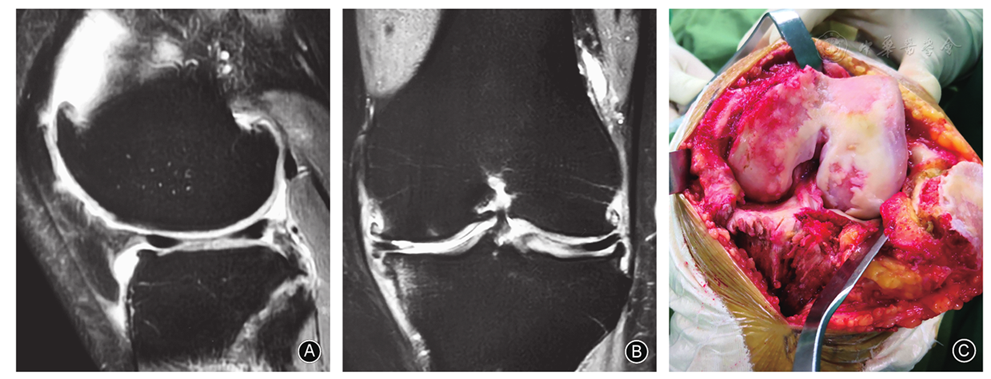

病情描述 患者主诉:左侧膝关节疼痛 诊疗经过: 哈尔滨医科大学附属第四医院骨科刘雪峰教授带领团队仔细检查阅片后发现病人有半月板损伤的症状,并伴有外侧间室的关节软骨严重损伤,这种情况已经不能单纯的通过关 ...